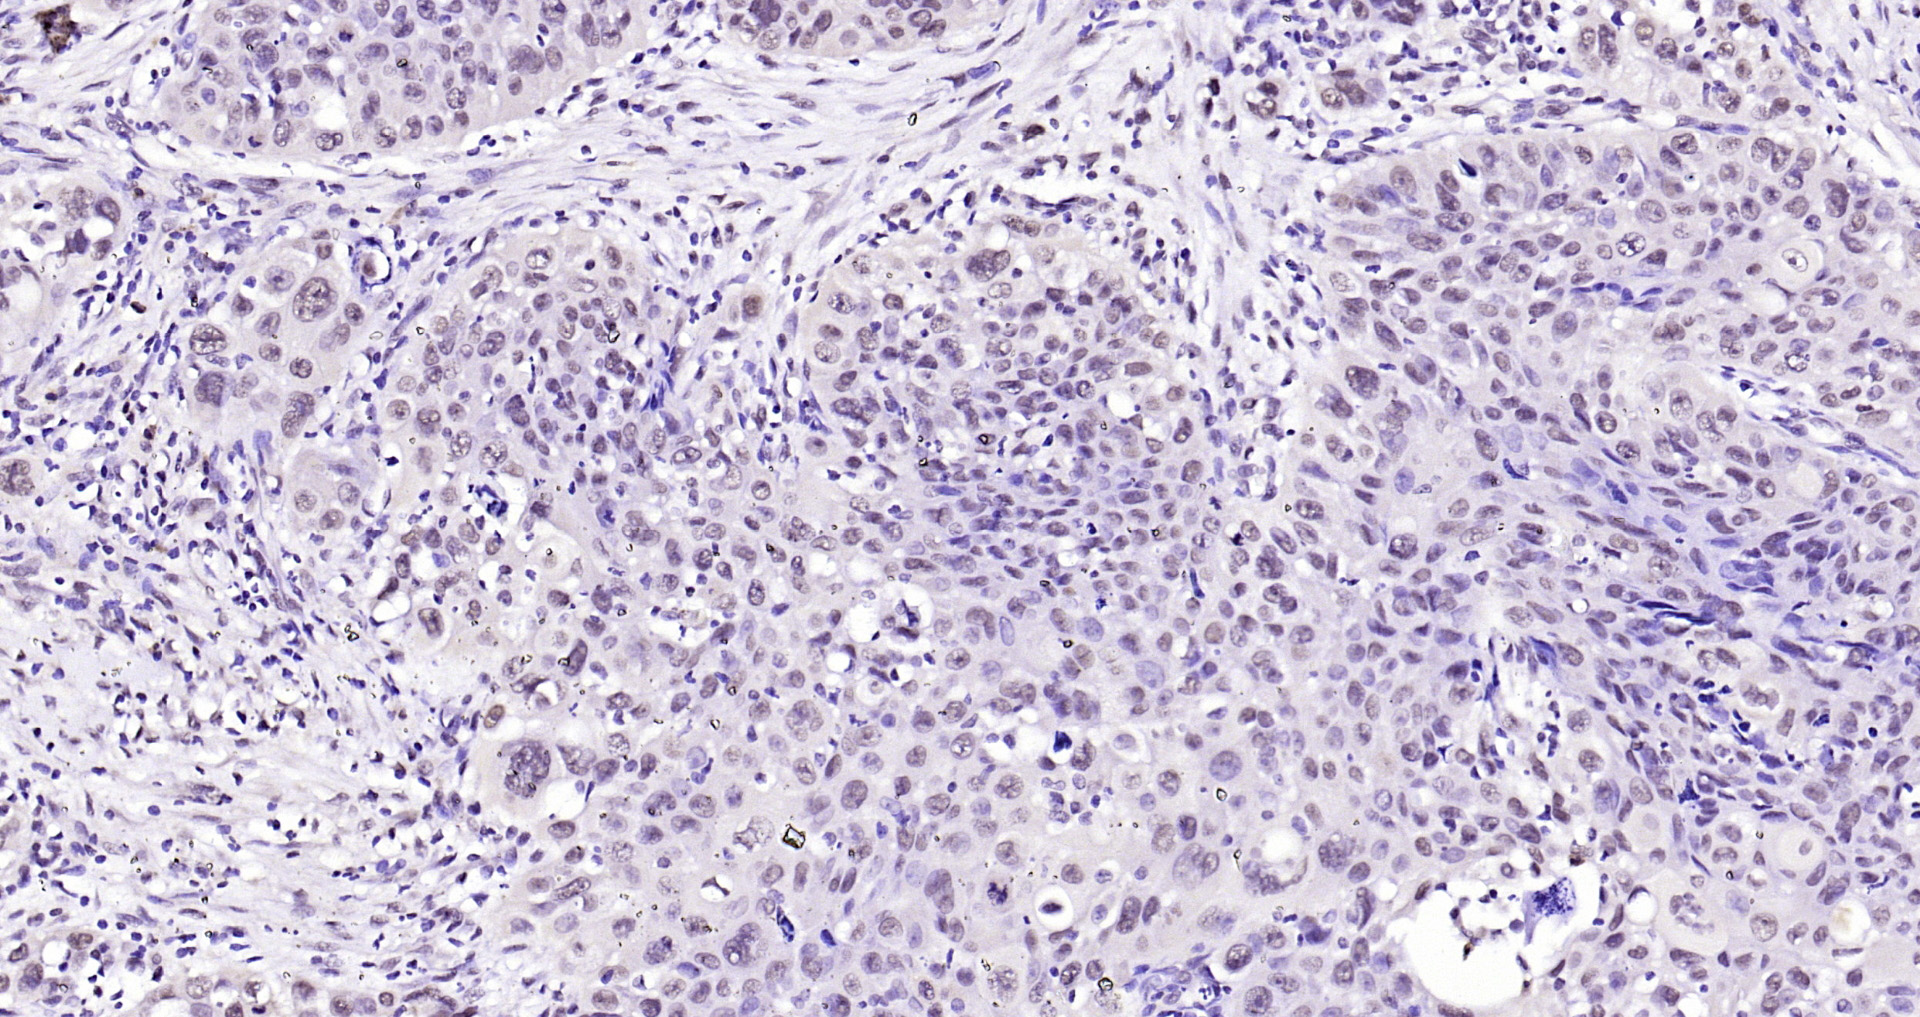

Paraformaldehyde-fixed, paraffin embedded Human colon cancer; Antigen retrieval by boiling in sodium citrate buffer (pH6.0) for 15min; Block endogenous peroxidase by 3% hydrogen peroxide for 20 minutes; Blocking buffer (normal goat serum) at 37°C for 30min; Antibody incubation with SOX9 Polyclonal Antibody, Unconjugated (bs-10725R) at 1:400 overnight at 4°C, DAB staining.